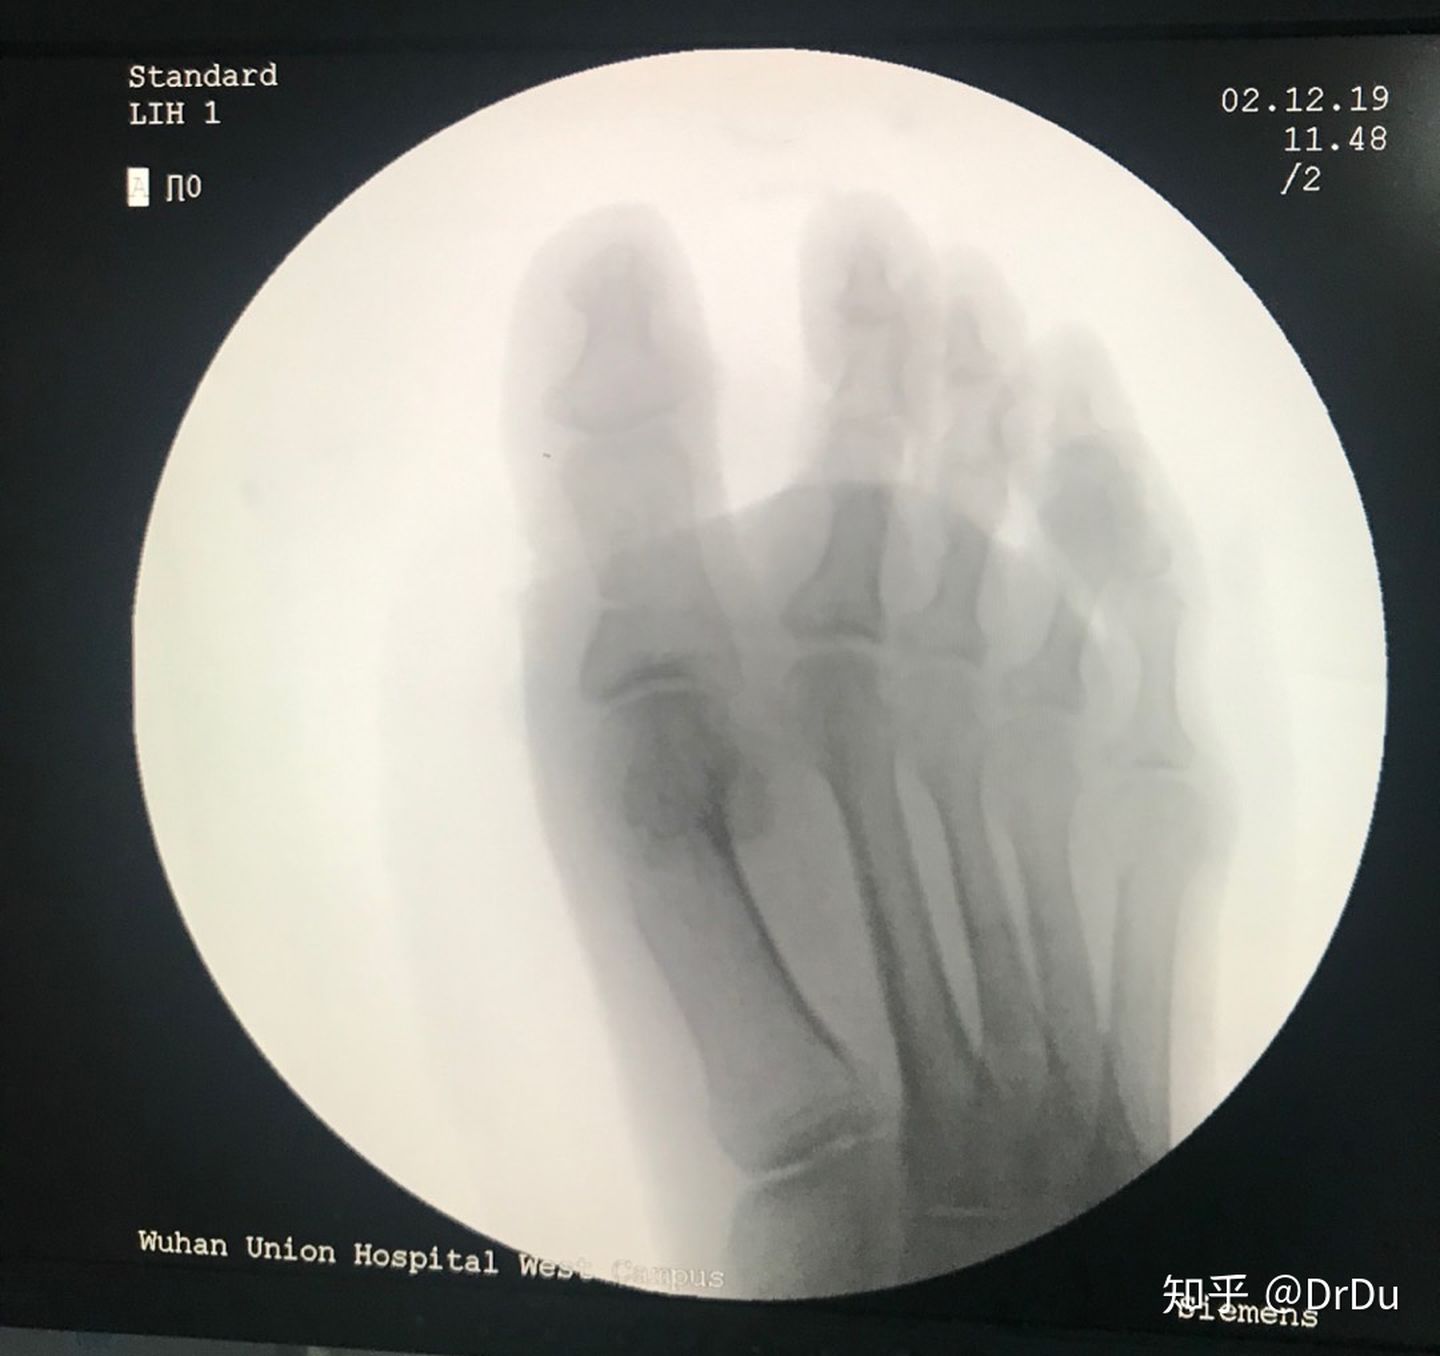

手术很顺利,手术前做了充分的准备,手术过程全部列了清单,贴在墙上,团队成员提前全部准备好。百密一疏,还是忽略了重要的一点,这次是我是自己给自己做手术,体位改变,右手来离断左脚的拇内收肌和外侧关节囊的时候,不顺手,很折腾了一会。还有就是开始止血带打的不够紧,有少许渗血,大约5毫升,影响到了手术视野。认识到这两个问题,第二只脚就顺利多了,完全没有出血。

摆锯截骨

做完一个,出血不到5毫升,可以忽略不计。